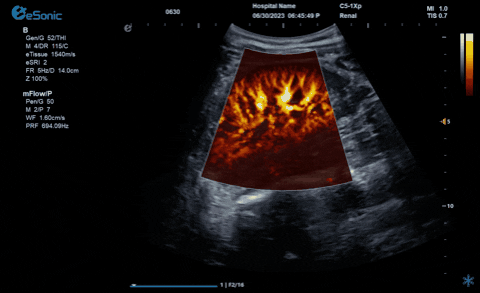

hjc888黄金城官网医疗的eHertz系列彩色多谱超声诊断系统凭借强大的RawVision?原数精准平台和SDBeam?软波声束合成技术推出专属的mFlow ?超微血流显像技术,该项技术可专用于极低速血流成像。彩色多普勒血流(CDFI)检查时,通常会将滤波器的频率设置为大约50hz,并随时调整标尺和增益,以便在背景噪声发生前显示小血管......